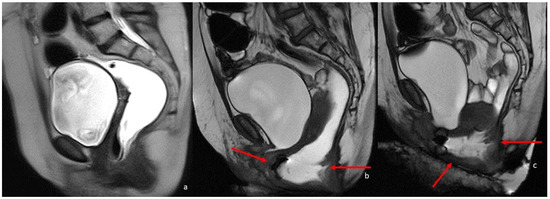

Figure 4.

A 74-year-old patient with rectal cancer. (a–c) are T2-weighted high-resolution images in the coronal, sagittal, and axial planes, respectively. The arrows point to the pathological parietal thickening of the walls of the rectum. (d) is an Axial DWI b1000 image.